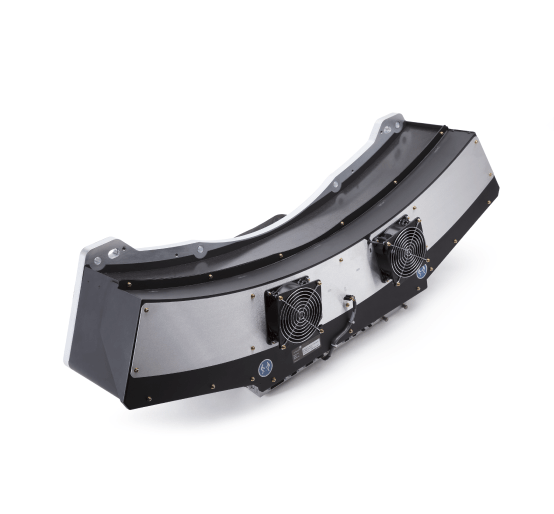

CTA Head and Neck Phantom for CT Scan and X-Ray Training。CT203924 富士フイルム互換リサイクルトナーを安く注文 Ecoink.in。タイトスカート/SUPER100'sウール/オーバーペーングレン。ENVYMのコートです。数回着用しました。発送の都合で圧縮かけさせていただきます。。Detectors.png。新品 ユニバーサルオーバーオール ショートカバーオール レディース。極美品 RIVE DROITE ツイードジャケット